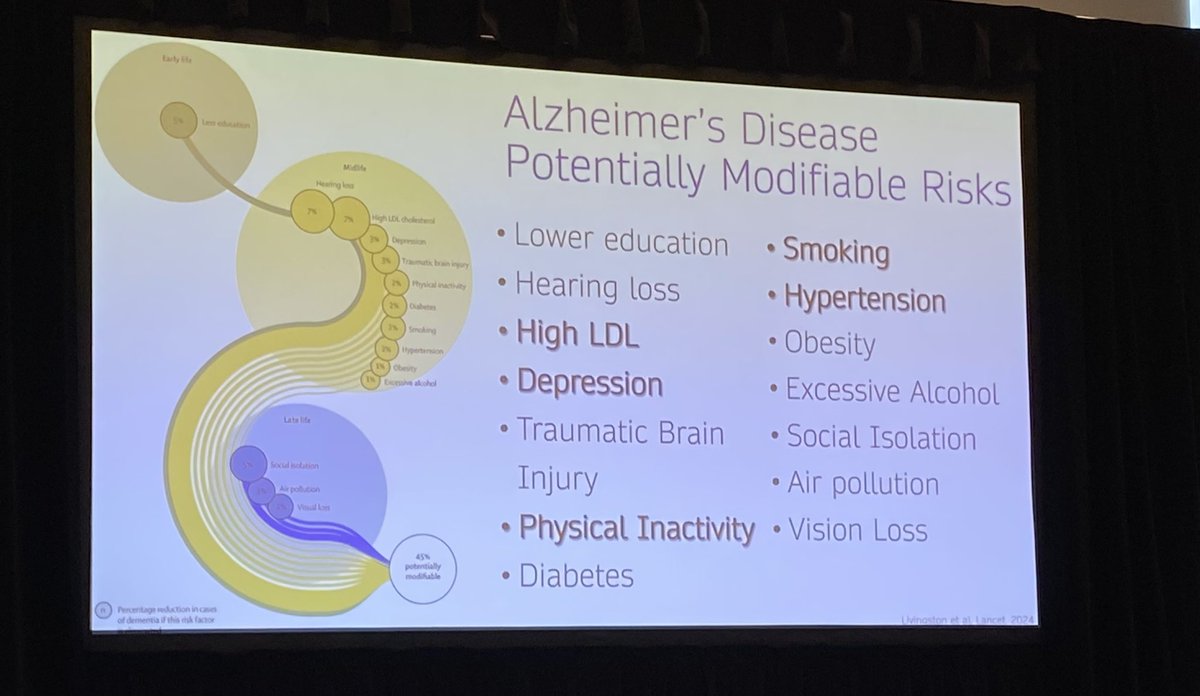

👴🏼 Ageing & RMDs at #ACR24

🧠 14 factors associated with dementia

❗️Justin Levenson tells us that if we could address all of these, we could reduce dementia risk by 45%!

@RheumNow https://t.co/SgC5KMohXy

Mrinalini Dey DrMiniDey ( View Tweet)